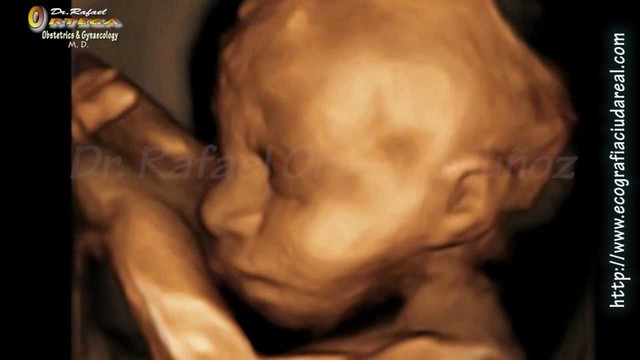

• Semana 12

Semana 12

-El feto entra al segundo trimestre.

-Existe menos riesgo de aborto.

-El feto sobresa desde ángulos diferentes.